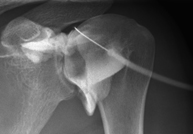

- RX Caderas pediatría

Estudio que, utilizando los rayos X, permite obtener una imagen de los huesos de la cadera y descartar luxaciones.